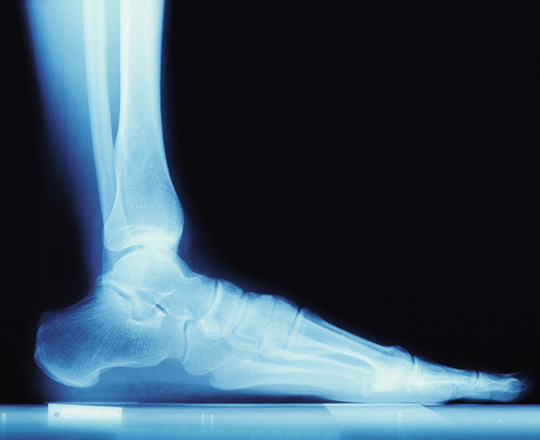

Röntgenbild Fuß Der Fuß ist ein anatomisches Wunder! Mit 26 Knochen, über 100 Muskel- und Bandansätzen, Sehnen, Bindegewebe bekommt er eine tragende Rolle.

Der Fuß besteht aus Zehen, Mittelfuß, Fußwurzeln und Rückfuß. In den Füßen befindet sich fast ein viertel der Knochen des menschlichen Körpers. Die Fußmuskulatur hat die Aufgabe, die Bewegungen des Fußes auszuführen und wird in die Gruppe der kurzen und langen Fußmuskeln unterteilt.

Die kurzen Fußmuskeln befinden sich am Fußskletett. Die langen Fußmuskeln liegen am Unterschenkel und übertragen Ihre Kraft durch Sehnen auf die Fußknochen. Das Fußgewölbe wird durch die Fußmuskulatur aktiv gespannt und durch Bänder passiv aufrecht erhalten. Zu unterscheiden sind das Längs- und Quergewölbe des Fußes, deren einwandfreie Funktion von großer Bedeutung ist. Einigen Erkrankungen des Fußes liegt ein Absinken des Fußgewölbes zugrunde.